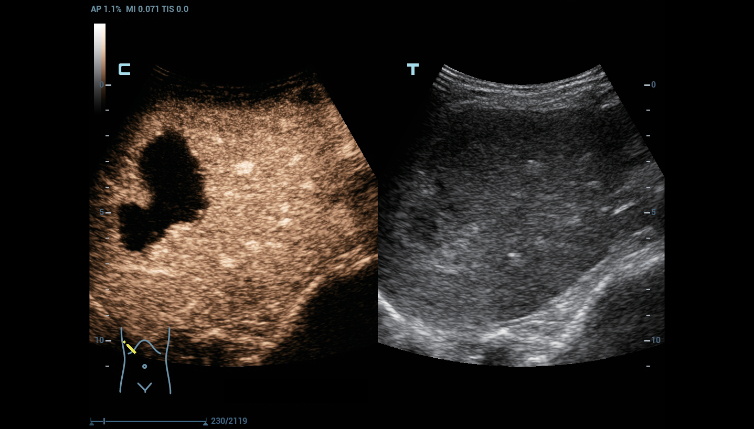

–Θ–Μ―¨―²―Ä–Α–Μ–Β–≥–Κ–Η–Ι –Ψ–±―ä–Β–Φ–Ϋ―΄–Ι –¥–Α―²―΅–Η–Κ ―¹ –≤―΄―¹–Ψ–Κ–Ψ–Ι –Ω―Ä–Ψ–Η–Ζ–≤–Ψ–¥–Η―²–Β–Μ―¨–Ϋ–Ψ―¹―²―¨―é

–Θ–Μ―¨―²―Ä–Α–Μ–Β–≥–Κ–Η–Ι –Η –≤―΄―¹–Ψ–Κ–Ψ–Ω–Μ–Ψ―²–Ϋ―΄–Ι –Ψ–±―ä–Β–Φ–Ϋ―΄–Ι –¥–Α―²―΅–Η–Κ –Ψ–±–Β―¹–Ω–Β―΅–Η–≤–Α–Β―² –Ω―Ä–Β–≤–Ψ―¹―Ö–Ψ–¥–Ϋ–Ψ–Β –Κ–Α―΅–Β―¹―²–≤–Ψ –≤–Η–Ζ―É–Α–Μ–Η–Ζ–Α―Ü–Η–Η –≤ –Α–Κ―É―à–Β―Ä―¹―²–≤–Β –≤ ―Ä–Β–Ε–Η–Φ–Α―Ö 2D, –Π–î–ö, 3D/4D –¥–Μ―è –±–Ψ–Μ―¨―à–Β–Ι –¥–Η–Α–≥–Ϋ–Ψ―¹―²–Η―΅–Β―¹–Κ–Ψ–Ι ―É–≤–Β―Ä–Β–Ϋ–Ϋ–Ψ―¹―²–Η –Η –Ω–Ψ–≤―΄―à–Β–Ϋ–Η―è –Κ–Α―΅–Β―¹―²–≤–Α –Η―¹―¹–Μ–Β–¥–Ψ–≤–Α–Ϋ–Η―è;